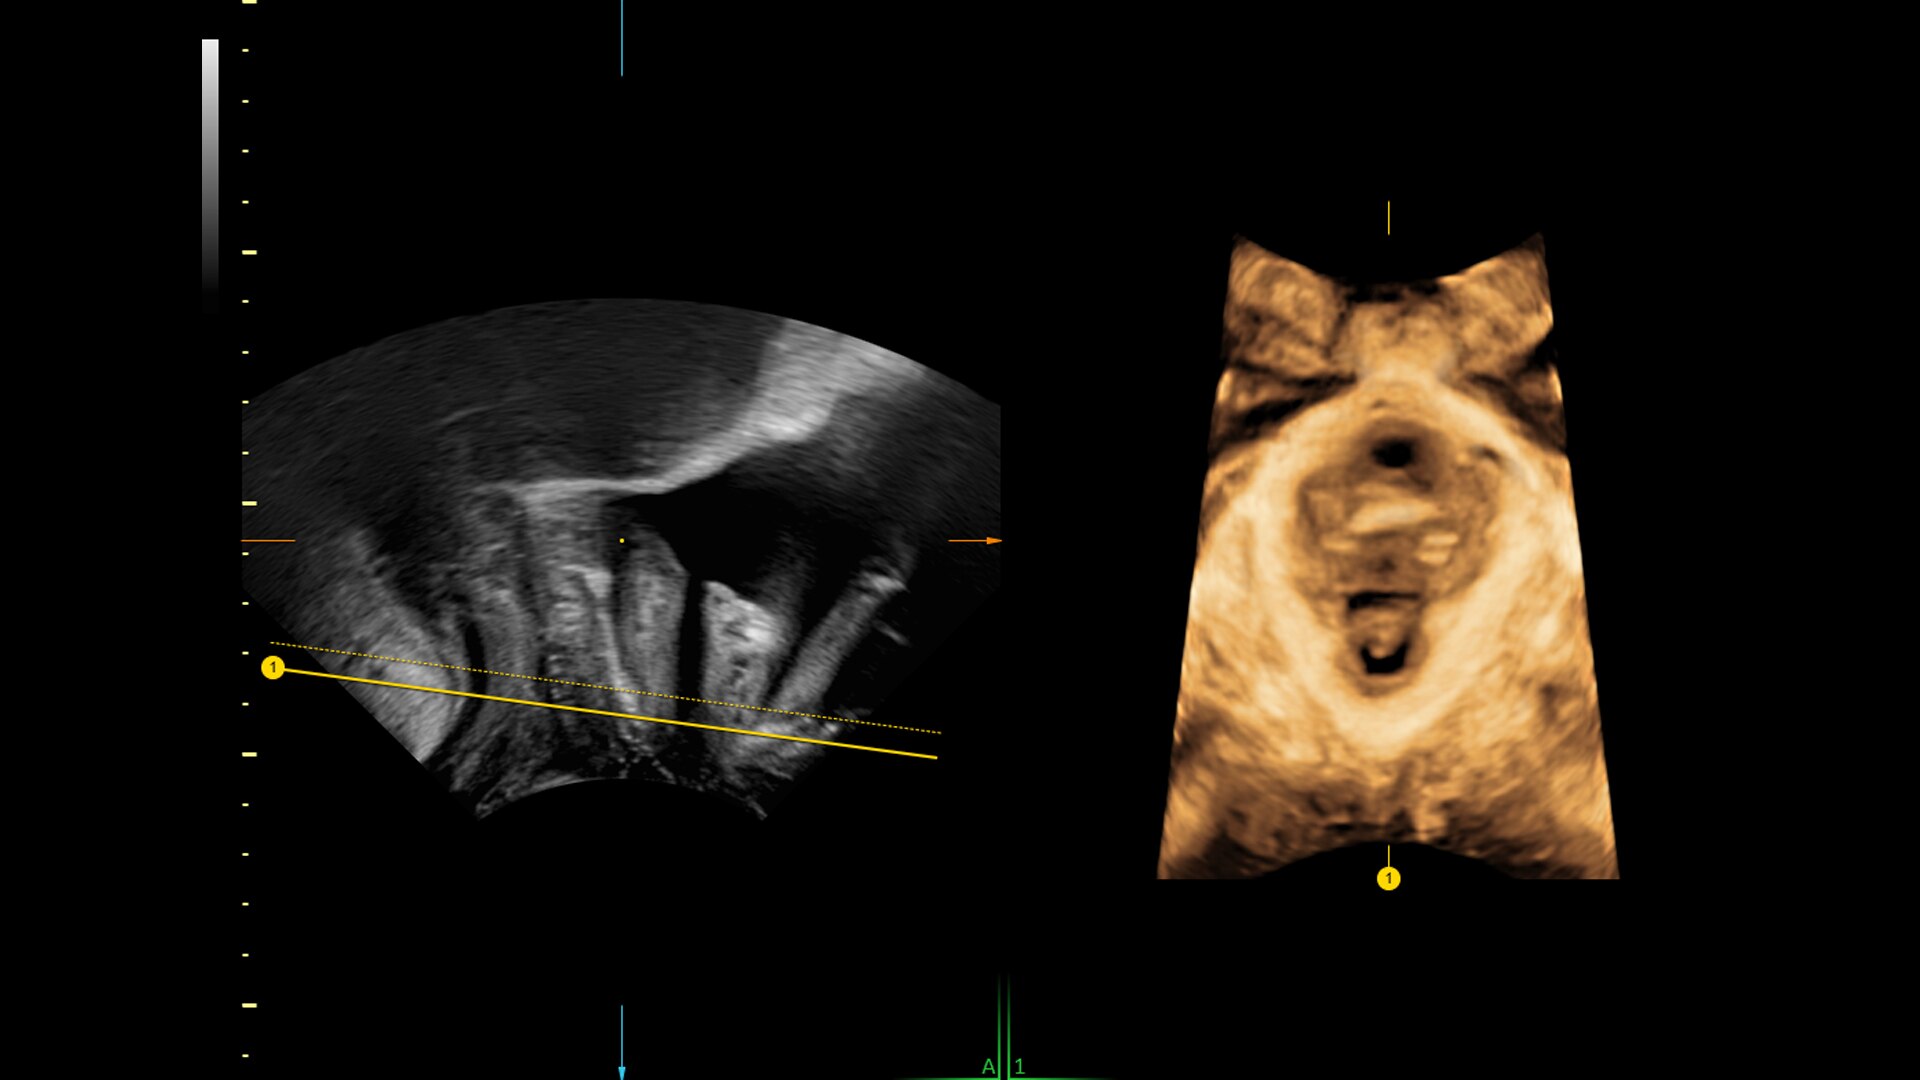

SonoPelvicFloor

Reduce exam time by up to 75% with SonoPelvicFloor. Simplify and speed up exams with automated plane alignment and automated measurements for more consistent reproducible results.